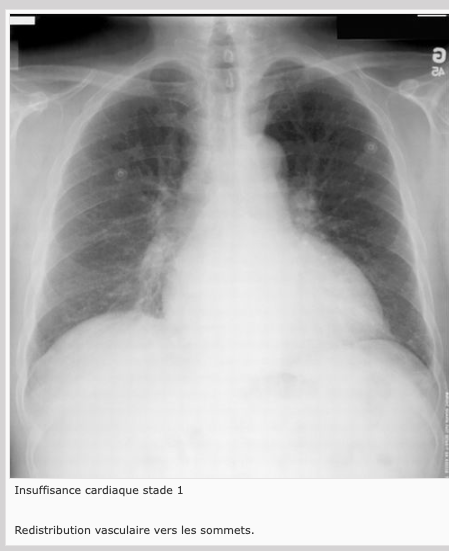

1) Redistribution vasculaire: vaisseaux des sommets apparaissent aussi ou plus proéminents qu’aux bases, ce qui est le contraire de la normale.

IC: Signes radiologiques de la redistribution vasculaire

les vaisseaux des sommets apparaissent aussi ou plus proéminents qu’aux bases, ce qui est le contraire de la normale.